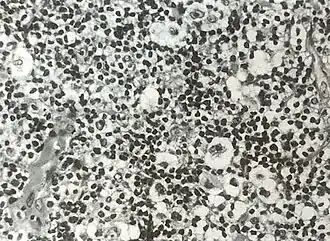

![]() Микропрепарат: биоптат лимфоузла. Характерная клетка Рид — Березовского — Штернберга | |

Лимфома Ходжкина (синонимы: лимфогранулемато́з[8][9], болезнь Ходжкина, злокачественная гранулёма) — злокачественное заболевание лимфоидной ткани, характерным признаком которого является наличие гигантских клеток Рид — Березовского — Штернберга, обнаруживаемых при микроскопическом исследовании поражённых лимфатических узлов.

Обнаружение гигантских клеток Рид-Березовского-Штернберга и их одноядерных предшественников, клеток Ходжкина, в биоптате есть обязательный критерий диагноза лимфогранулематоза. По мнению многих авторов, только эти клетки являются опухолевыми. Все остальные клетки и фиброз есть отражение иммунной реакции организма на опухолевый рост. Главными клетками лимфогранулематозной ткани, как правило, будут мелкие, зрелые Т-лимфоциты фенотипа CD2, CD3, CD4 > CD8, CD5 с различным количеством В-лимфоцитов. В той или иной степени присутствуют гистиоциты, эозинофилы, нейтрофилы, плазматические клетки и фиброз. Соответственно различают четыре основных гистологических типа:

- Смешанноклеточный вариант — примерно 30 % случаев лимфомы Ходжкина. Наиболее частый вариант в развивающихся странах, у детей, пожилых людей. Чаще болеют мужчины, клинически соответствует II—III стадии болезни с типичной общей симптоматикой и склонностью к генерализации процесса. Микроскопическая картина отличается большим полиморфизмом со множеством клеток Рид-Березовского-Штернберга, лимфоцитов, плазмоцитов, эозинофилов, фибробластов.